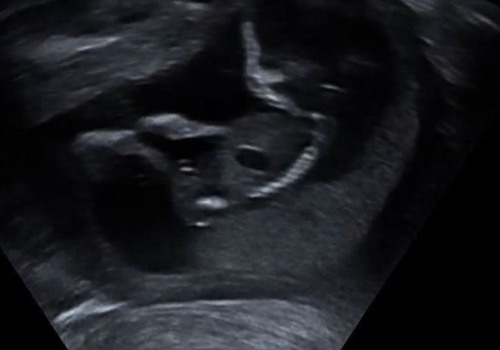

Iemand een idee?☺️ 13+2

Is dit een duidelijke foto?